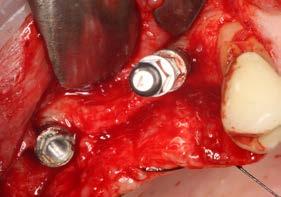

Explantación atraumática y recambio de implantes mal posicionados y afectados por periimplantitis sumado a la utilización de implantes estrechos y cortos. Enfoque mínimamente invasivo de un caso de atrofia ósea moderada

42 | INVESTIGACIÓN CLÍNICA